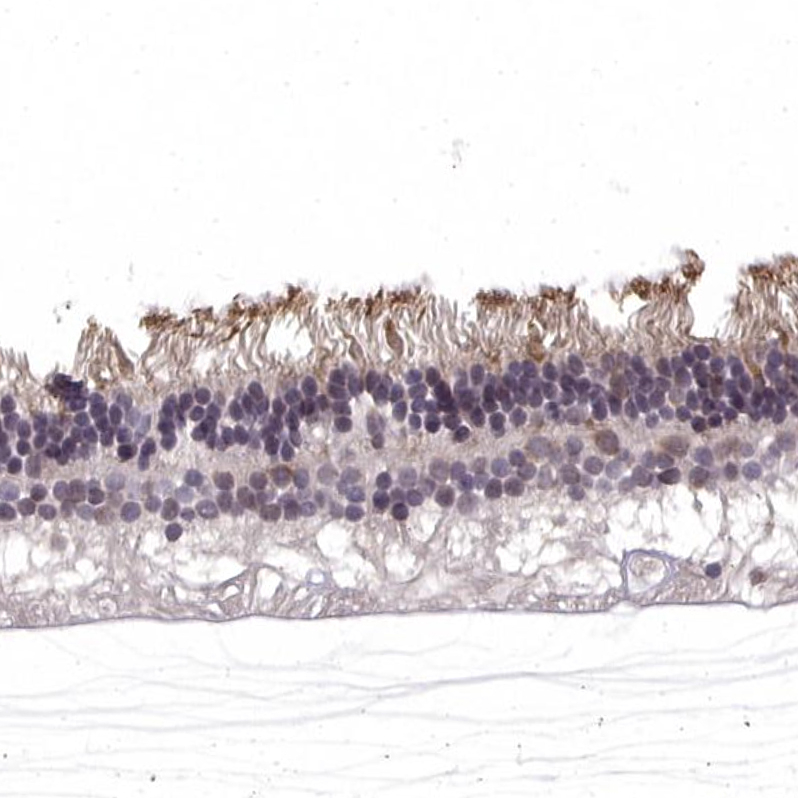

Immunohistochemical staining of human eye retina shows moderate membranous positivity in rods.